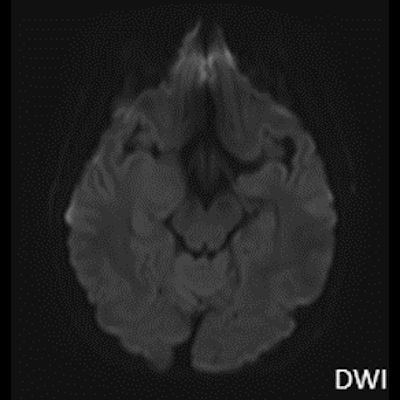

- B) Lezyon difüzyon görüntüde izo-hiperintens, ADC haritalamada hafif hiperintens izlenmiş olup (oklar) diffüzyon kısıtlılığı göstermemektedir. Lezyonun anterior kesiminde kontrastlı serilerde yamalı kontrast tutulumları (oklar) mevcuttur. MR spektroskopide lezyon düzeyinden elde olunan multivoksel görüntülerde kolin pikinde artış ve NAA da azalma (oklar) dikkati çekmektedir. Kolin/kreatinin oranı 1.76 olarak ölçülmüştür.